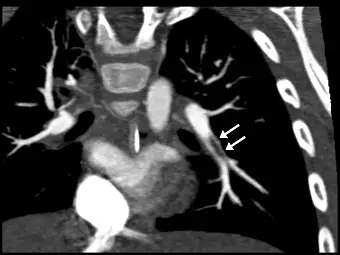

幼兒呼吸困難,胸部電腦斷層顯示肺動脈栓塞( pulmonary embolism )如下圖箭號處所示。此影像沿著病灶所在的血管長軸來呈現,是用了下列何種後處理技術?

- 影像特徵:這是一張胸部電腦斷層肺動脈血管攝影(CTPA)的重組影像。影像中顯示了縱膈腔結構、心臟以及充滿高密度對比劑的肺動脈。

- 病灶特徵:圖中兩個白色箭號所指之處,可以觀察到在明亮的左側肺動脈分支管腔內,存在著長條狀、低密度的「充盈缺損(filling defect)」。這是典型肺動脈栓塞(pulmonary embolism, PE)的直接影像學表徵。

- 切面特徵:值得注意的是,此影像並非標準的軸狀面(axial)、冠狀面(coronal)或矢狀面(sagittal)。這是一個將彎曲的肺動脈血管「拉直」或「沿著血管走向」切開的 2D 剖面圖,使得整條血管的長軸與管腔內的血栓能完整呈現在同一個平面上。

- (A) multiplanar reconstruction(MPR):正確。多切面重組(MPR)允許操作者從 3D 體積